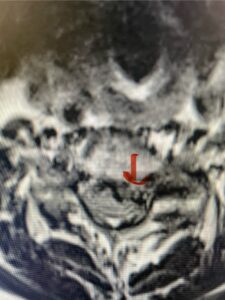

Another patient, a 77 year-old female, presents with pain, numbness, and weakness of her arms and difficulty with balance over a 6-month period. MRI revealed severe osteophytic disease at C5-C7 with cord compression (Fig. 4). Further work-up by fine-cut cervical CT to evaluate the nature of compression revealed a completely calcified osteophyte (Fig. 5). Although the patient had a good lordosis and a posterior cervical approach would accomplish an adequate decompression, we elected to perform a two-level anterior cervical discectomy and fusion. This particular osteophyte is formidable because of its size but the compression was all anterior and would be a less invasive approach. Fortunately, during the procedure, the patient had a fair amount of osteoporosis which allowed the osteophyte to be drilled and bit away with considerable ease. Interestingly, the C6 7 osteophyte which was more a sheet of osteophyte was more challenging to remove. In the end the decompression went well, and we placed two interbody devices filled with bone graft with plates at each level (Fig. 6). The patient had a nice recovery with immediate reduction of pain and numbness. This case demonstrates the importance of recognition of cervical myelopathy in its early stages. A significant reversal of function is generally the rule if the patient has appropriate correlative findings on exam and MRI, particularly with long tract distribution weakness development within a year time period.

Figs 4a: Sagittal and axial T2-weighted cervical MRIs demonstrating large osteophyte worse at C5-6 compressing spinal cord more eccentrically to the left (red arrows)

Fig 4b